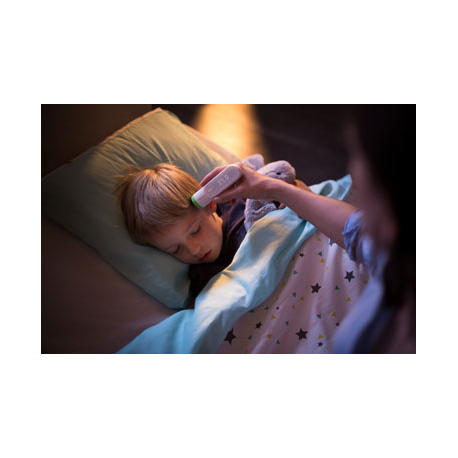

Ce thermomètre connecté vous permettra de ne plus choisir entre confort et précision. Il offre la possibilité de prendre la température de plusieurs personnes en toute simplicité, de manière extrêmement précise, indolore et totalement hygiénique. Connecté à votre smartphone, il vous donne les conseils qu'il faut pour vous aider à mieux traiter les épisodes de fièvre et à prendre soin de vous-même et de votre famille.

Le thermomètre connecté prend la température de l'artère temporale, considérée comme le meilleur moyen de mesurer les variations de température, car l'influx de sang vient directement du cœur. Equipé de la technologie brevetée HotSpot Sensor, il utilise 16 capteurs pour prendre plus de 4000 mesures en 2 secondes et trouver le point le plus chaud de l'artère temporale. Un simple scan, sans contact, à 1 centimètre du front suffit. Contrairement aux autres thermomètres, il n'entre en contact avec aucun fluide corporel comme la salive, la transpiration ou le cérumen. C'est la manière la plus hygiénique de prendre sa température et il ne requiert pas d'être nettoyé entre chaque mesure.